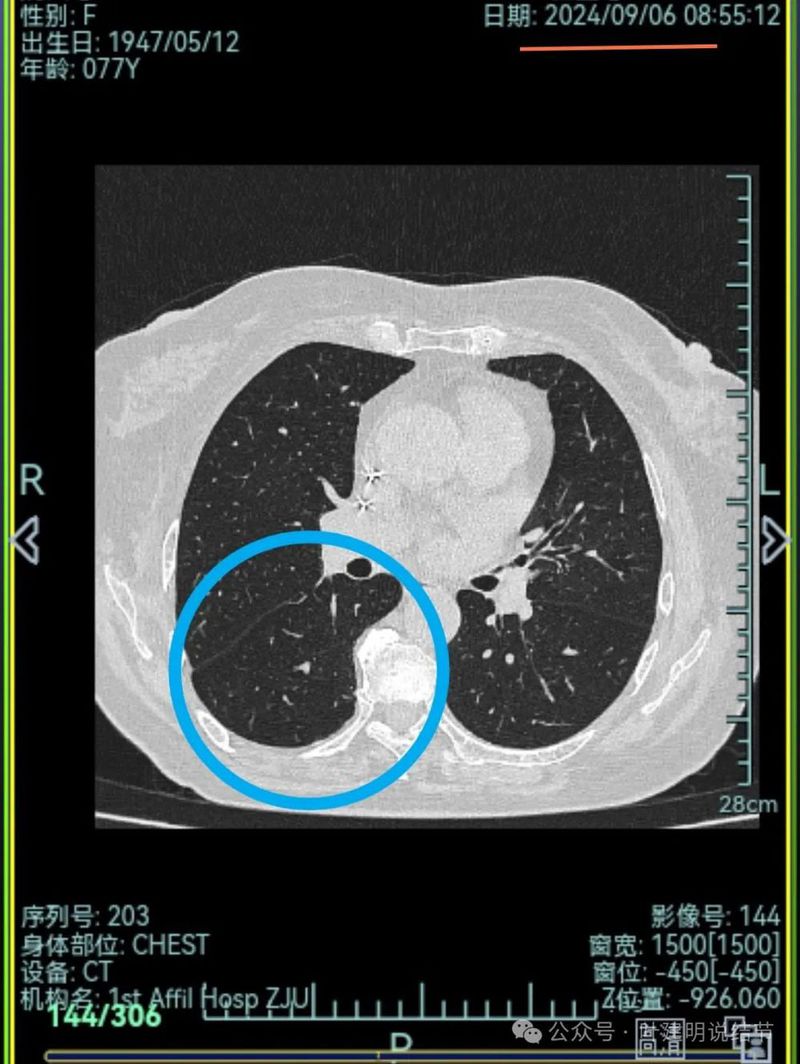

再来看2024年9月时的关键影像:

中叶处病灶不见了。

下叶背段伴血管征的病灶也不见了。

不单是右中叶以及右下叶的病灶吸收消失了,两肺其他病灶也基本上都不见了,唯独右上后段的病灶仍在而且有进展!再加上此灶原来单看也像恶性的,所以这位结友是感染与肿瘤并存,右上病灶基本上肯定是恶性的,而且是浸润性腺癌。

右下混合密度结节,有明显血管进入,轮廓较清,瘤肺边界较清,单灶单处看也像恶性些;

左下胸膜下混合密度结节,边缘不平有毛刺,但毛刺不是很锐利,与胸膜侧紧贴,没有明显牵拉。

右中叶混合密度结节,有血管进入,表面不平,略有胸膜牵拉,但感觉病灶显散,聚拢性不够。